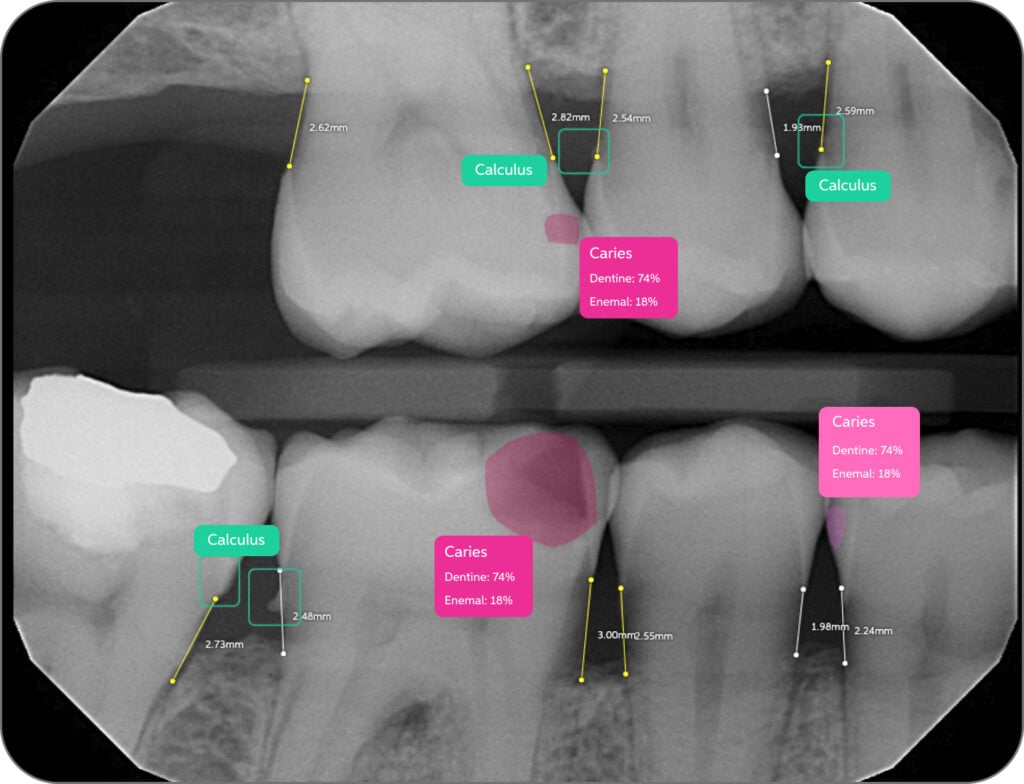

New clinicians now have a quiet partner reviewing every radiograph, flagging possible decay, bone loss, calculus, and more — right there on the screen, in color.

Now, when a provider reviews radiographs, they’re seeing them through both human and AI eyes. Pearl flags the areas of concern, helps confirm findings, and elevates the quality of treatment planning across the board.

Pearl’s visual clarity also helps patients understand their diagnoses.

“The patient says, ‘Yeah, I see that — it’s in color.” Kerbel noted. “They don’t understand shades of gray, but they understand pink, red, green. It’s easier for them to believe what we’re saying.”